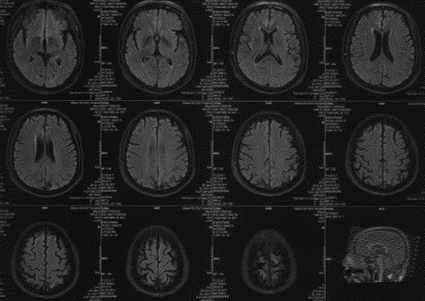

辅助检查(头颅核磁)

波科支架怎么样径技-弓上病例大赏|第210期·右侧颈内动脉球囊扩张术+支架植入术_https://www.jmylbn.com_新闻资讯_第9张

波科支架怎么样径技-弓上病例大赏|第210期·右侧颈内动脉球囊扩张术+支架植入术_https://www.jmylbn.com_新闻资讯_第10张